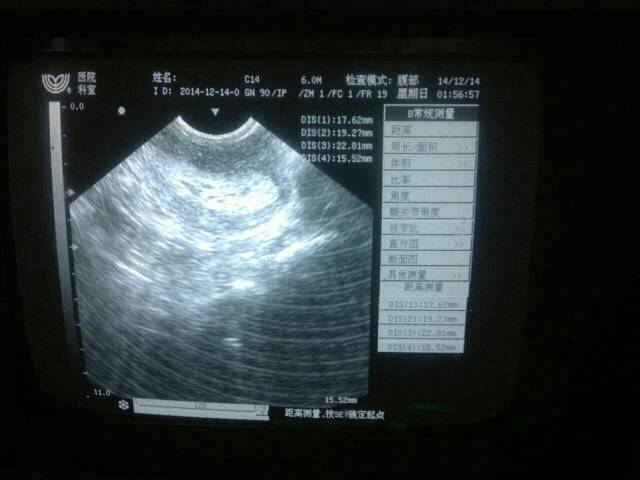

内膜厚度达到22 做阴超医生怀疑怀孕 不敢确定 我想问问怎么办?48天没来月经 试纸测试没怀孕 点击展开 母婴用户82122519 2014-12-16 21:13 为您推荐: 其他回答 你好,根据你的描述,如果目前B超没有发现宫内妊囊,建议最好可以查一个的Hcg看看值是否正常,排除怀孕的可能祝健康! xldy521 2014-12-16 22:57 相关问题 想问下,我用试纸测试弱阳性,怀孕五十天,我做阴超彩超都不见孕囊,但是医生说没流产现象,内膜厚1 3 请问医生,宝宝三个月了,我7月8号来月经第一天,7月17号晚上跟老公在一起回怀孕吗?我可以吗避孕药 我现在怀孕多久了,医生帮我算算,我上个月月经是6月1号来的,现在是7月12号了